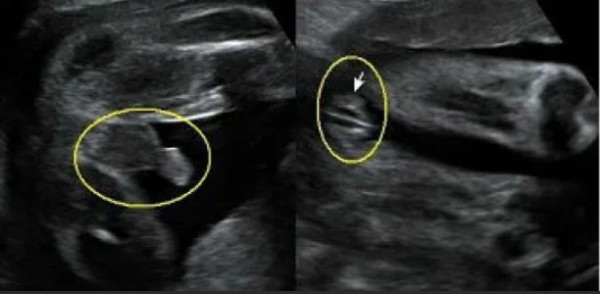

Пол на 14 неделе беременности по узи

Пол на 14 неделе беременности по узи 88 фото